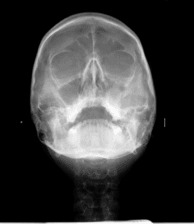

Зъбните снимки, независимо дали са секторни, панорамни зъбни снимки, телерентгенографии или друг вид се съхраняват на нашите сървъри неограничено дълго време.

Зъбните снимки са налични в няколко различни файлови формата - DICOM (DCM), PNG и JPG, което улеснява свалянето им на личните компютри.

Денталните медици могат с лекота да правят всички необходими обработки и измервания на дигиталните зъбни снимки, което улеснява подготовката за лечебния процес на пациента.